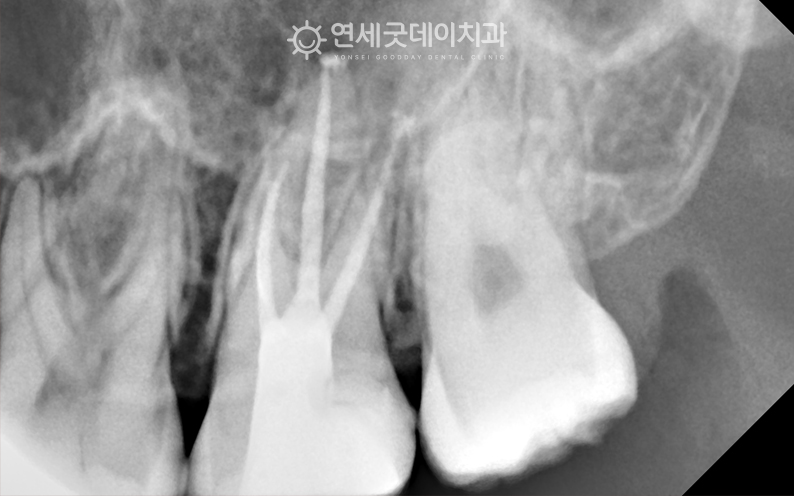

● 담당과 : 보존과 어금니 부위의 큰 충치를 주소로

#27, 36 부위에 큰 충치가 관찰되며

두 부위 모두 발치를 고려할 정도로 큰 충치였으나 또한 사진상 표시된 부위의 인접 치아는

신경치료를 통해 손상된 신경관을 제거 및 소독한 뒤 환자분은 치아 머리가 많이 손상된 상태였기 때문에

자연치아 살리기 과정 중 이후 약해진 치아를 보호하고

이어서 #27 부위도 신경치료를 진행하였으며

발치까지 고려할 만큼 심한 충치였음에도 연세굿데이치과는 오랫동안 자연치아 살리기 진료를 긴 치료 받으시느라 고생 많으셨습니다 :) ※ 모든 사진은 본인의 동의를 얻어 동일조건에서 촬영하였으며 |